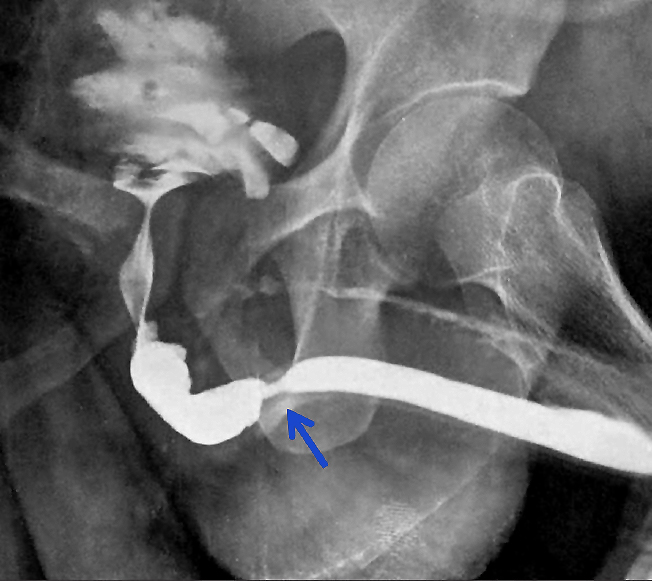

Retrograde Pyelogram - Urethral obstruction

A CT scan may reveal the presence of cancer, visible as a blockage.

A retrograde pyelogram is another kind of imaging test that uses contrast dye to improve imaging for the bladder, ureters, and kidneys. This procedure may be used in cases where an obstruction is suspected in the ureters or the kidney, such as a tumor, stone, blood clot, or stricture (narrowing of the tube).